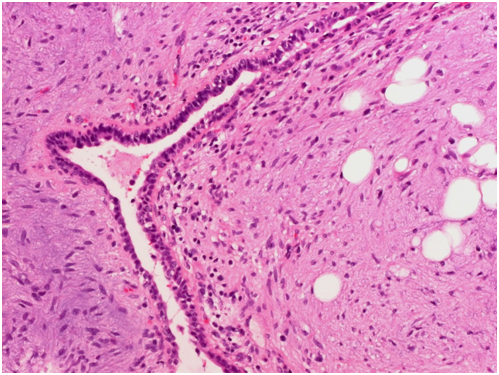

The tumorectomy specimen showed a tumor measuring 14.5x12x11cm and with a weight of 1123g. The lesion was multilobulated on cross sections with some myxoid-appearing areas. Microscopic examination revealed heterogeneity of the tumor. Most of the lesion showed cartilaginous and fatty differentiation with extensive chondroid and chondro-myxoid areas. Also present were narrow slit-like spaces lined by simple columnar and pseudostratified ciliated epithelium. Focally adjacent there was a mild chronic inflammatory infiltrate as well as strands of smooth muscle and focal calcifications. The lesion was well circumscribed and attached to it was a small amount of unremarkable lung tissue. The diagnosis made was chondroid hamartoma or more specifically giant chondroid hamartoma owing to its unusually large size.

Figure 4: Microscopic image showing slit-like spaces lined by simple columnar and respiratory-type epithelium, hematoxylin and eosin staining.